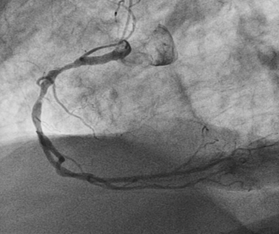

A 81year old gentleman presented to the emergency department accompanied by emergency physician and paramedics with typical angina symptoms for last 1hour associated with Dyspnoe, nausea  and vomitimg. The chest pain has subsided with administration of Morphin i.v. On arrival in the emergency department, one immediate 12-lead ECG  was done, that showed lateral wall  ST-elevated myocardial infarction (Figure 1). Wihout delay as per the current guidelines one emergency  angiogram was done, that revealed one occluded Ramus diagonalis branch of Left anterior descending artery(Figure-2) and one Plaque rupture in mid segment of right coronary artery with subtotal occlusion (Figures 2 & 3). Immidiately the coronary flow in Ramus diagonalis -2 was regained and the culprit lesion was treated with 2 drug eluting stents  2,25X14mm size, the end result was TIMI III Flow in Ramus diagonalis -2. During the procedure the EKG showed ST elevation in lead II, III and aVF with intermittent Atrioventricular Block III, Blood pressure was 100/56mm Hg and heart rate was 65 per minute. We decided to perform the angioplasty of Right coronary artery. The flow in right coronary artery was restored and the culprit lesion as treated with 2 Drug eluting stents 3.0X19 mm and 3,5X 14mm, resulting in TIMI III Flow. The ST elevation leads II, III and aVF were settled.

Figure 2 Coronaryangiography.

Figure 3 Coronaryangiography.